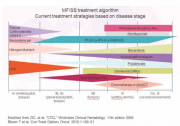

| 11:51, 30 בנובמבר 2017 | CTCL2.png (קובץ) |  |

115 קילו־בייטים | Motyk | 1 | |